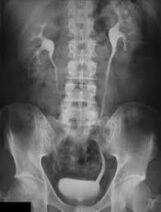

Durante una radiografía abdominal (vientre), usted está acostado sobre una mesa. Es probable que le pidan que cambie de posición o que se siente si se necesita más de una vista. Usted necesitará contener la respiración y permanecer inmóvil mientras se toma rápidamente la imagen.